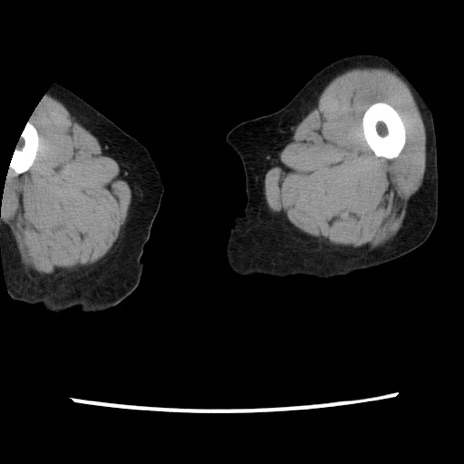

症例1(横断像)

【症例】80歳代女性

【主訴】腹痛

【現病歴】8時間前から腹痛あり来院。

【既往歴】糖尿病、脂質異常症、子宮体癌にて子宮全摘術

【身体所見】意識清明・会話良好だが腹痛で苦悶様、全腹部にわたって反跳痛と圧痛あり

【データ】WBC 13600、CRP 0.14、LDH 224、CK 90